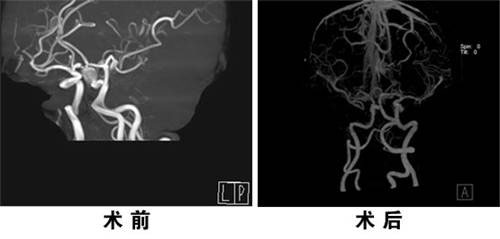

日前,北京燕化医院神经外科成功为一位高难度颅内动脉瘤患者实施了夹闭手术。该患者5月前不明原因出现右眼视物模糊。行头颅CTA提示:右侧颈动脉C1段见大小约9.8×10.9mm囊袋状影。脑动脉管壁的厚度为身体其他部位同管径动脉的三分之二,周围缺乏组织支持,但承受的血流量大。该患者手术难度在于:1、瘤体大;2、瘤颈宽;3、肿瘤位置不好,在颅底部,不利于手术。肿瘤紧邻前床突与视神经管,手术需要在显微镜下磨开视神经管,磨掉前床突,显露瘤颈,在这过程中稍有不慎就有可能损伤视神经或动脉瘤破裂,造成不可挽回的损伤。另外过近夹闭动脉瘤,可能出现载瘤动脉的阻塞;过远夹闭动脉瘤,则导致所谓“动脉残余”(尽管仅1~2mm),此残余以后可进一步扩张,导致再次破裂。通过手术,既要做到把动脉瘤彻底夹闭,又不影响功能区,以尽量保证病人术后的生活质量。

在大家的共同努力下,历时4小时30分钟,终于完美的夹闭了动脉瘤颈。

术后,经过医护人员精心管理和护理,患者体温、血压等生命体征一直在正常范围,未出现并发症。现患者已治愈出院。